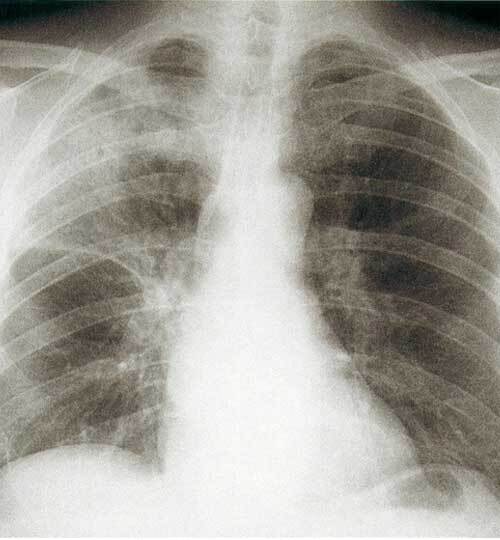

La radiographie thoracique met en évidence un infiltrat alvéolaire ou alvéolo-interstitiel systématisé ou non, éventuellement associé à une pleurésie. Il est recommandé de la réaliser dans les trois jours : en l’absence de foyer, on peut arrêter l’antibiothérapie (révision du diagnostic).

L’échographie pleuropulmonaire est aussi une option qui peut être proposée en première intention sous réserve d’une formation préalable du praticien ; elle est particulièrement indiquée chez les patients ayant une insuffisance respiratoire aiguë rendant difficile la réalisation d’une radiographie de bonne qualité.

Les imageries de contrôle ne sont pas recommandées de façon systématique en cas d’évolution clinique favorable et en l’absence de risque de cancer bronchique.

Le scanner n’a pas de place pour le diagnostic en ambulatoire mais un scanner de dépistage doit être réalisé à distance (après un délai d’au moins 2 mois) chez un patient tabagique âgé de plus de 50 ans.